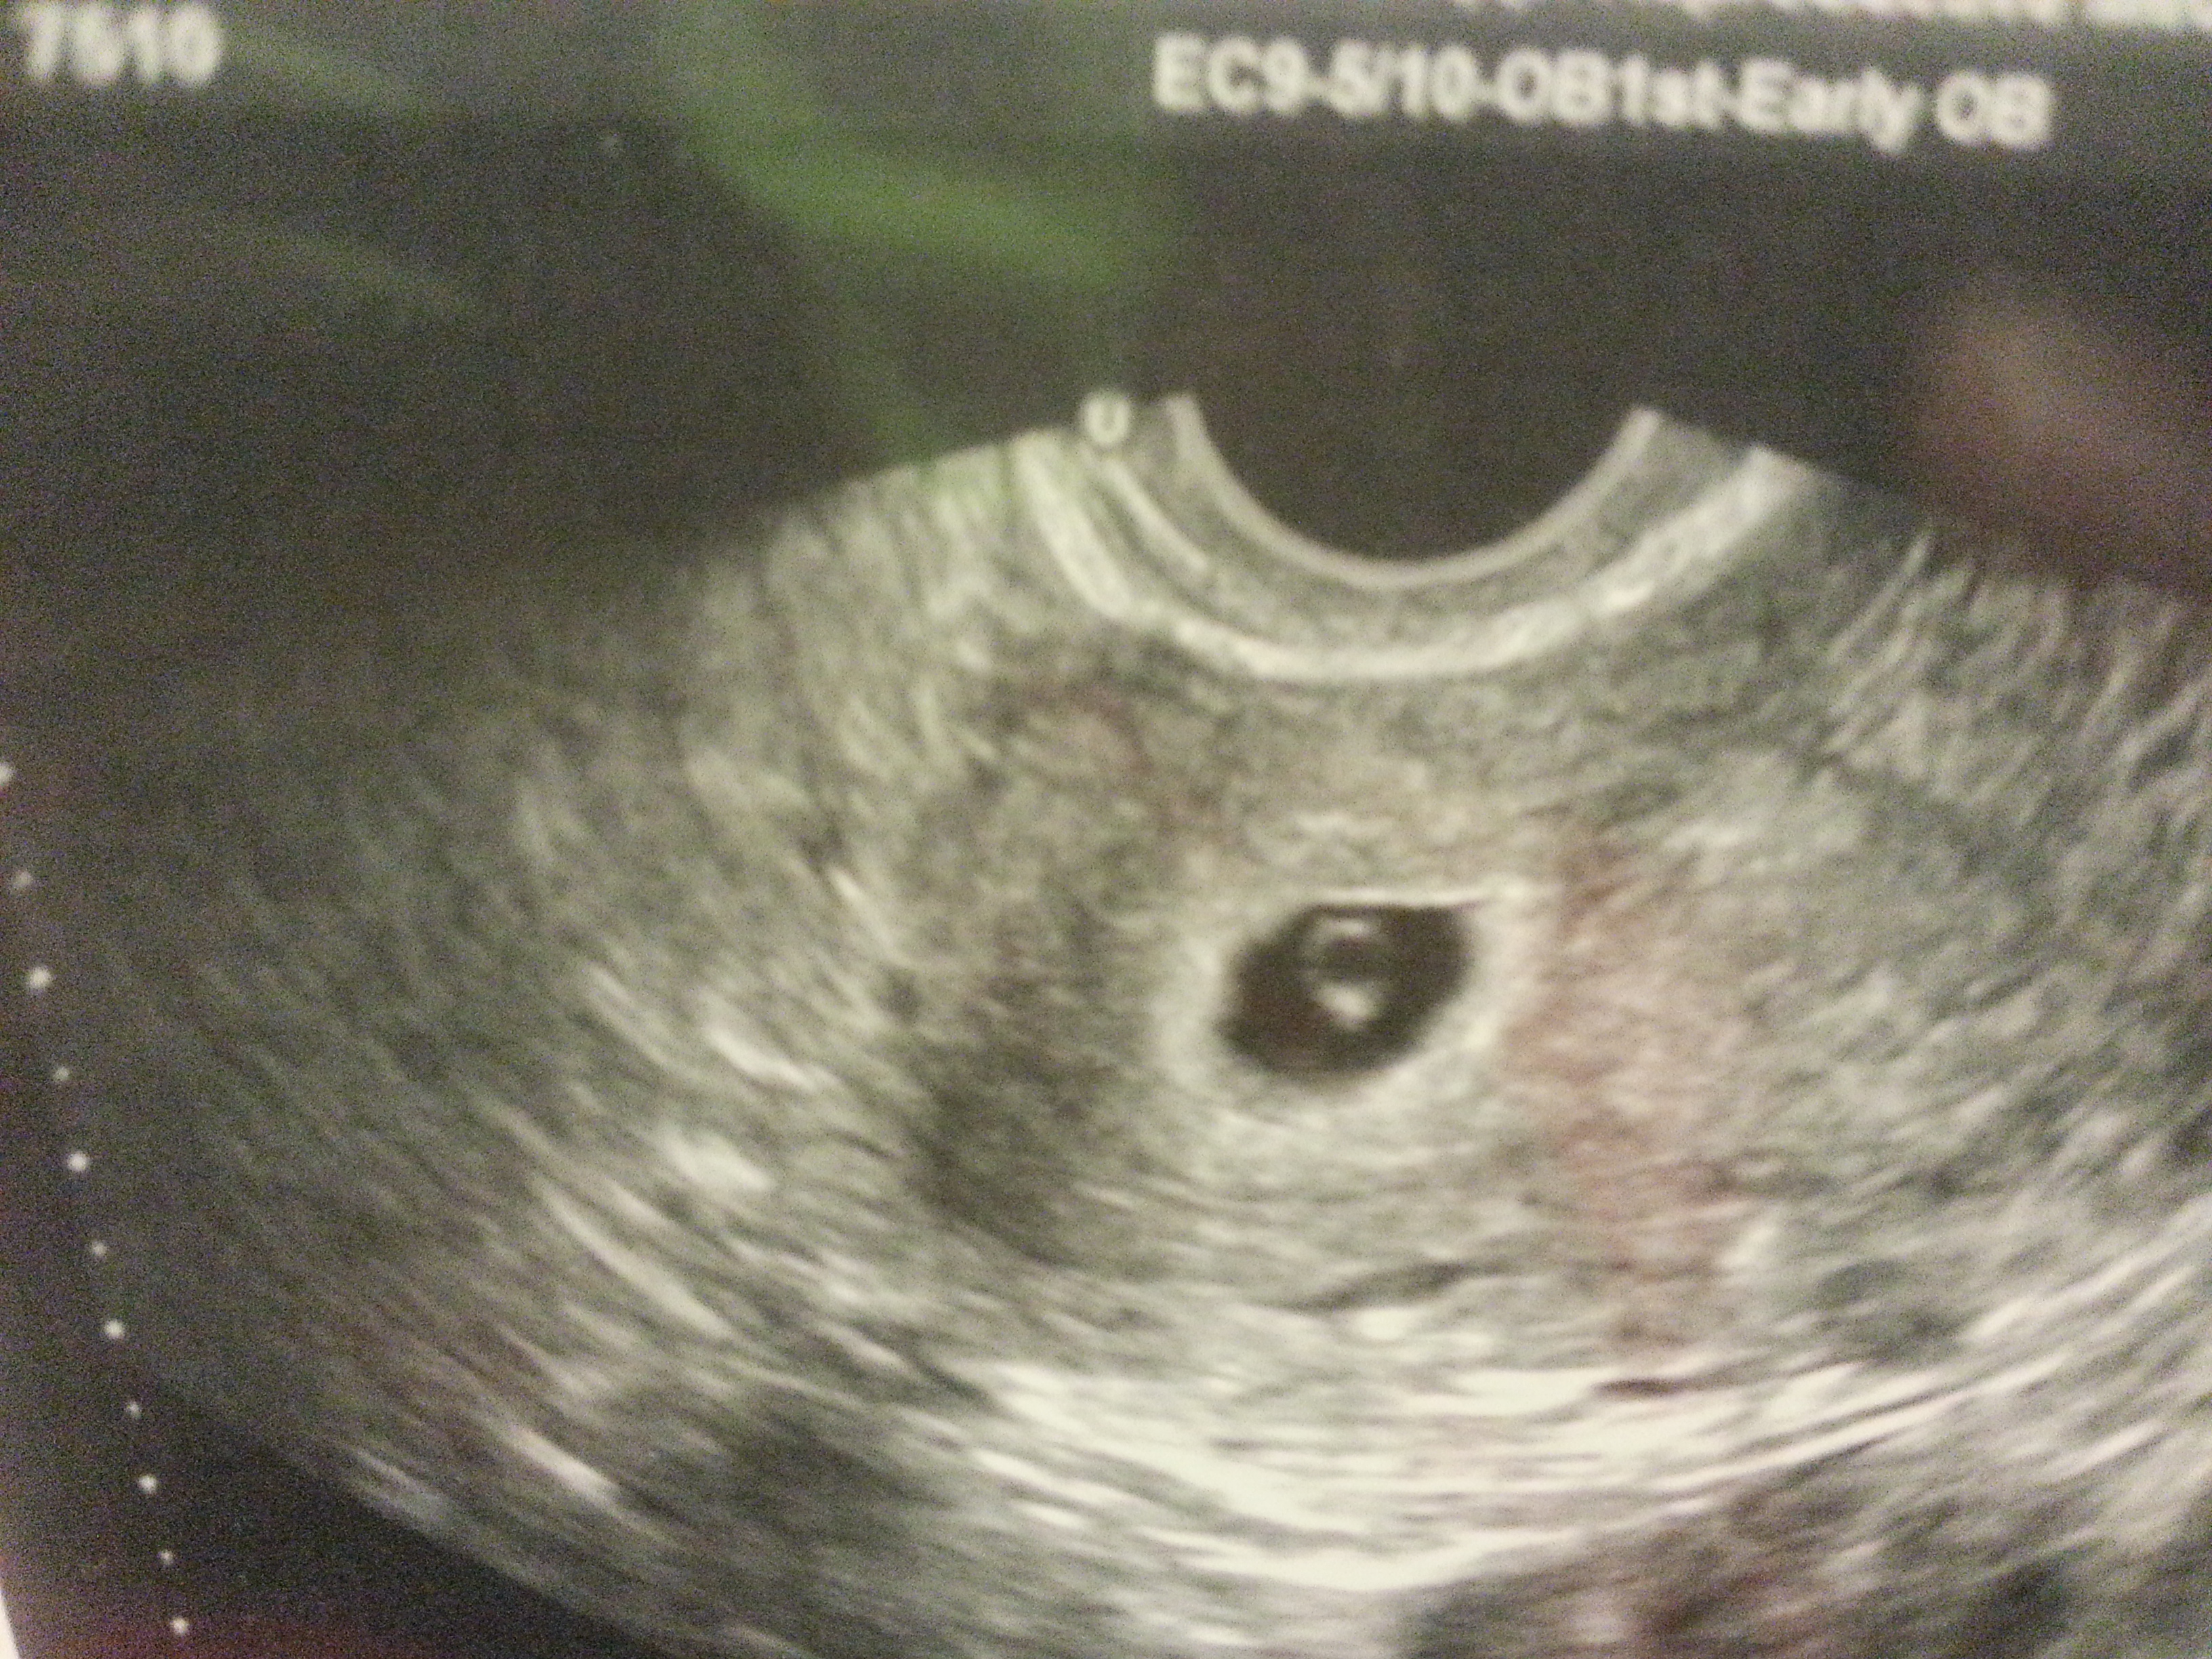

here are 2 US's (done at same time) of my first child at 5 wks 5 days and hr was 96.15 (guess what it was :))

Attachment 22518

They were both T/V but first pic was done by my OB and the other 2 pic are done by a specialist since that was my 6th pregnancy.